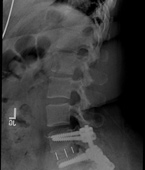

Before

After